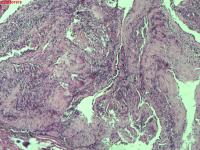

右肺上叶开口处 气管镜咬检

性别

男

年龄

65岁

临床诊断

一般病史

肺TB

标本名称

大体所见

右肺上叶开口上缘处可见肉芽增生,予咬检。

感觉:炎性纤维组织增生